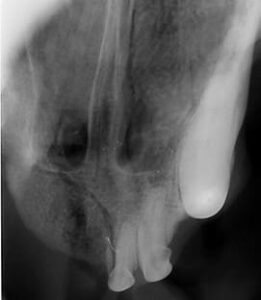

Diagnostic testing will start with a thorough oral examination and periodontal probing, dental X-rays, and computed tomography (conventional or cone beam computer tomography=CBCT). In rare cases, an MRI may be recommended.ย

Images of an oral tumor before surgery.

ย ย ย ย